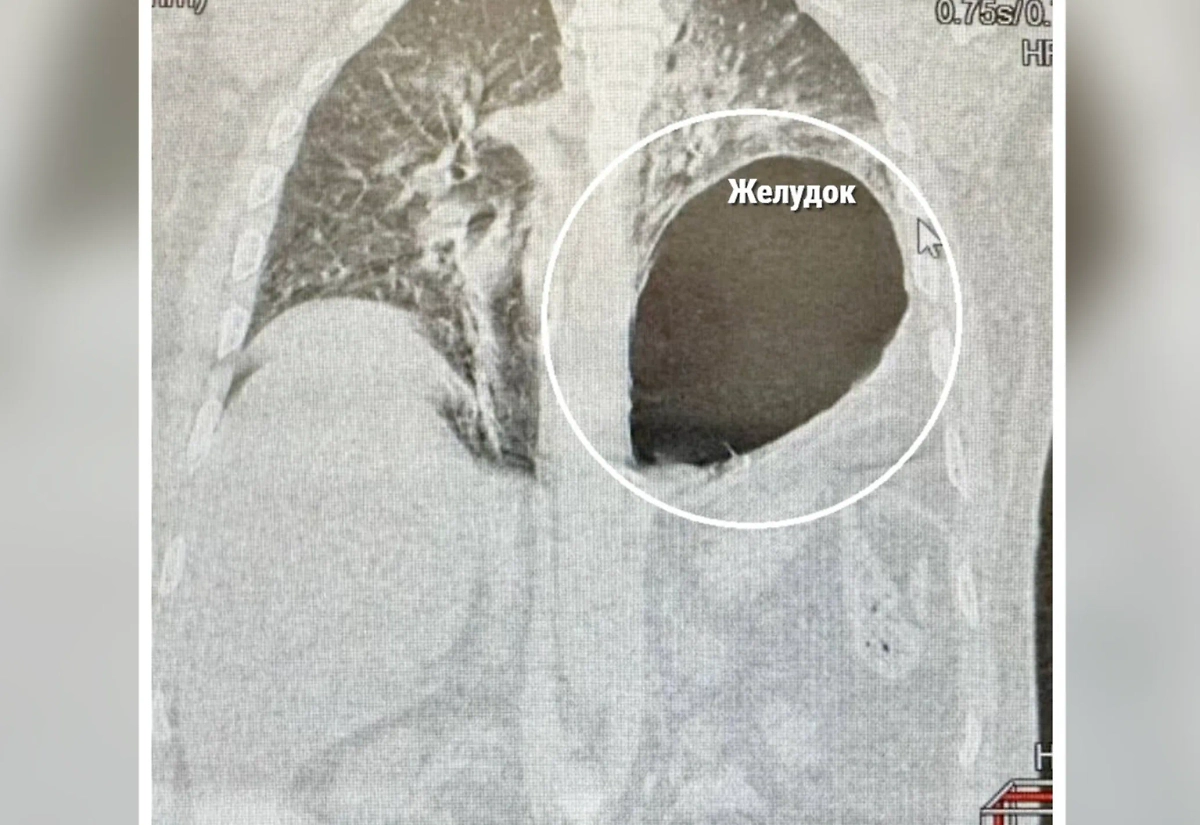

При поступлении в больницу пациент испытывал серьёзные затруднения с движением и дыханием. Обследование показало, что у него закрытая травма грудной клетки и живота, несколько переломов ребер, а также разрыв диафрагмы, из-за чего желудок переместился в плевральную полость, что невооружённым глазом видно даже на съёмках компьютерной томограммы.

Фото © Министерство здравоохранения Московской области

«Левое легкое было спавшим, а желудок практически оказался в плевральной области, что сдавило сердце и средостение. Состояние пациента было критическим, и время играло решающую роль. Мы провели экстренную лапаротомию, вернули желудок на место, дренировали левую плевральную полость и зашили дефект диафрагмы», — рассказал хирург Сергей Поликарпов.